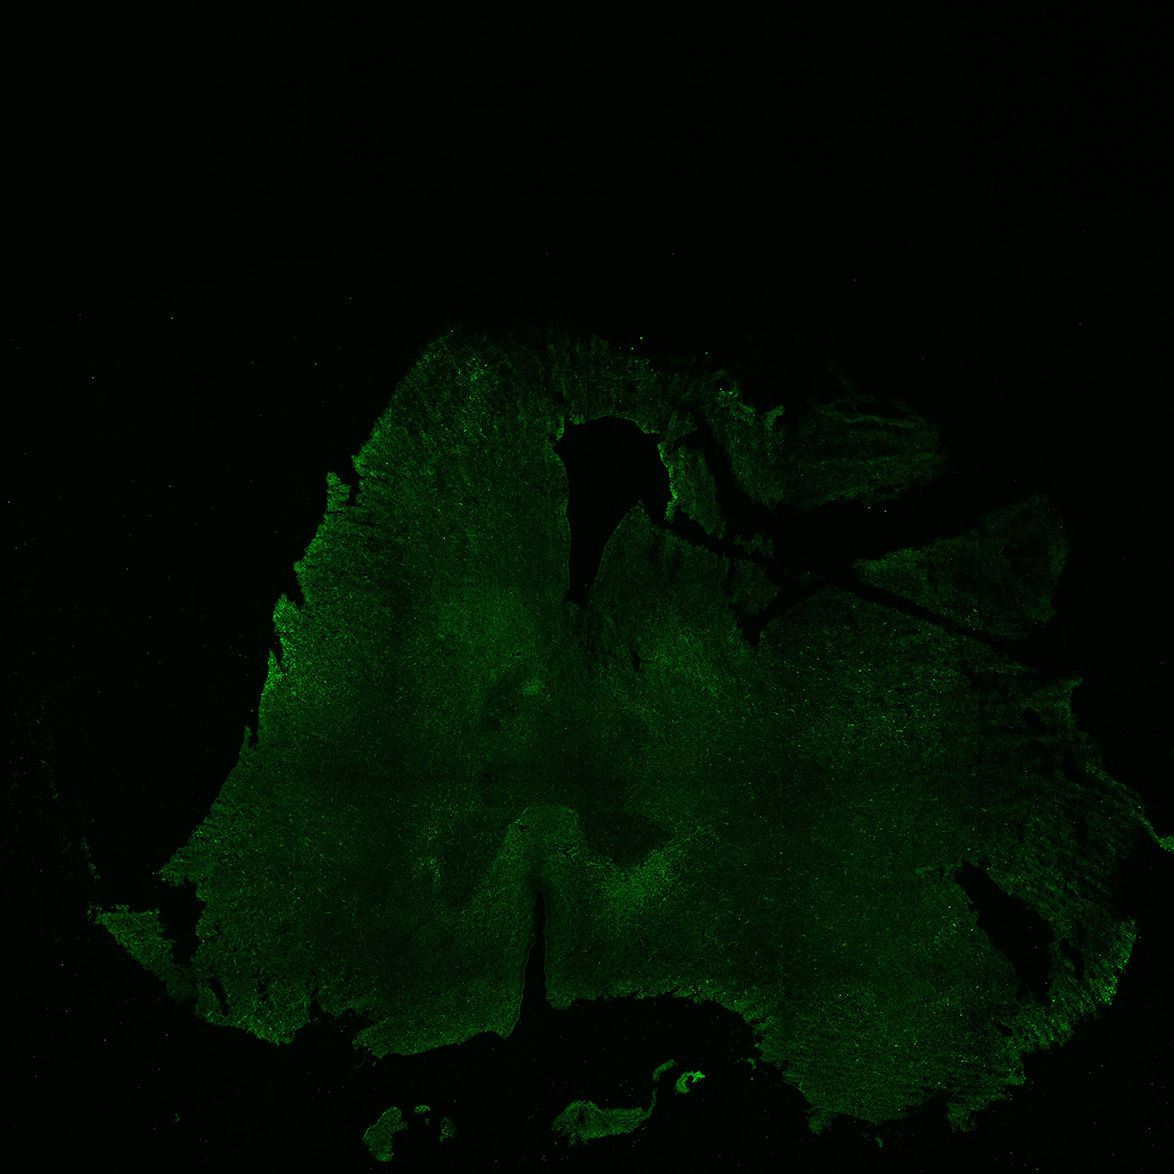

22PCW

DAPI

22PCW human midbrain

GFAP

TH

Merged